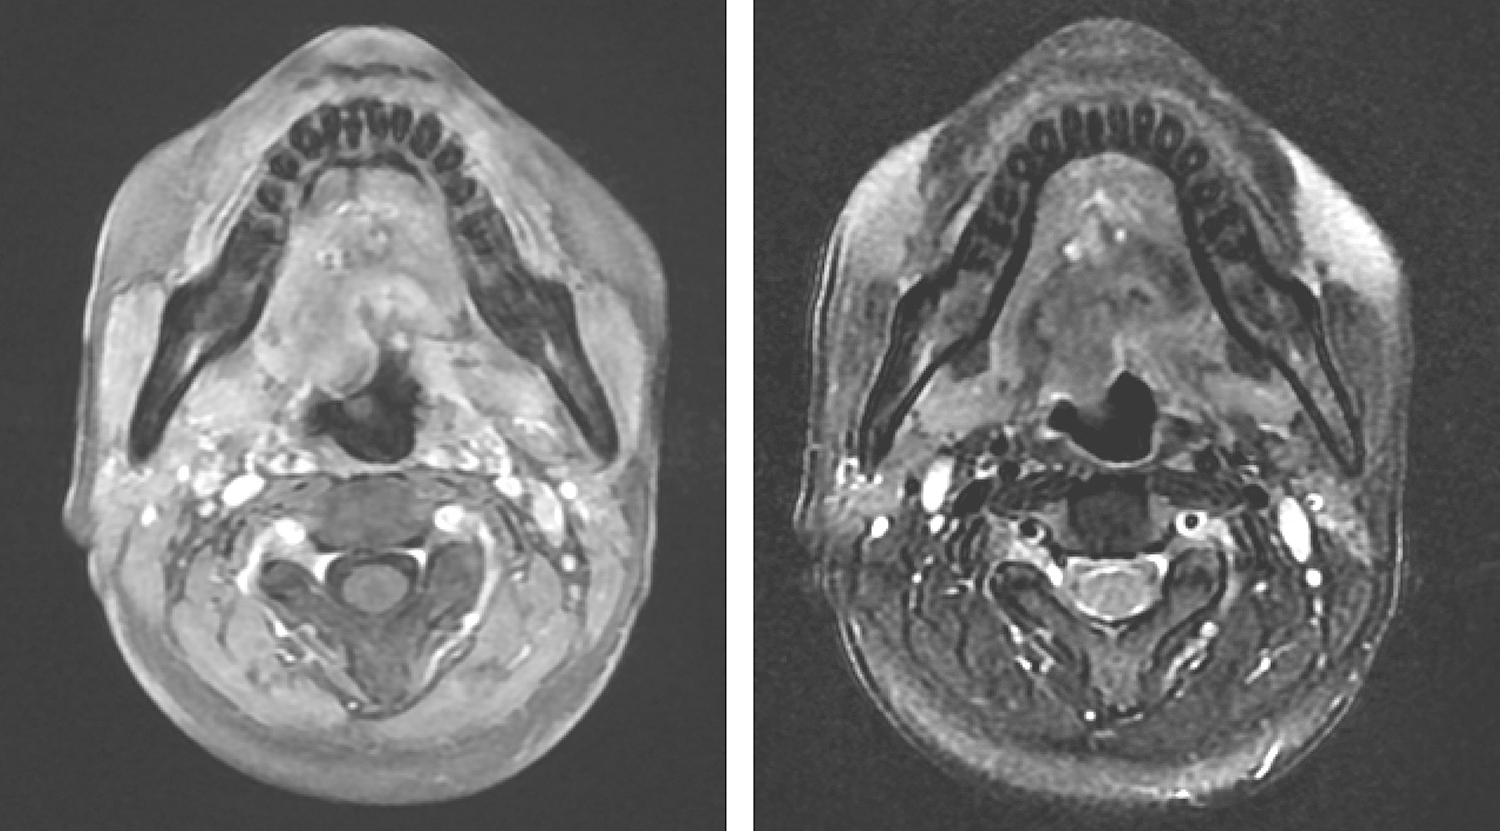

7.2013年3月12日口咽MR平扫检查

“舌根肿瘤,与2012年10月19日MRI比较:①舌根及口底区肿瘤,不规则状,边界欠清,呈不均匀强化,伴范围约2.8cm×3cm×2cm,可符合低度恶性肿瘤(图4),同前大致相仿,请结合临床考虑。②扫描范围内双侧颈深组多个淋巴结,大者约0.7cm,同前大致相仿。③扫描范围内余颈部未见明确异常。

图4口腔MRI示舌根及口底区肿瘤形状不规则不均匀强化